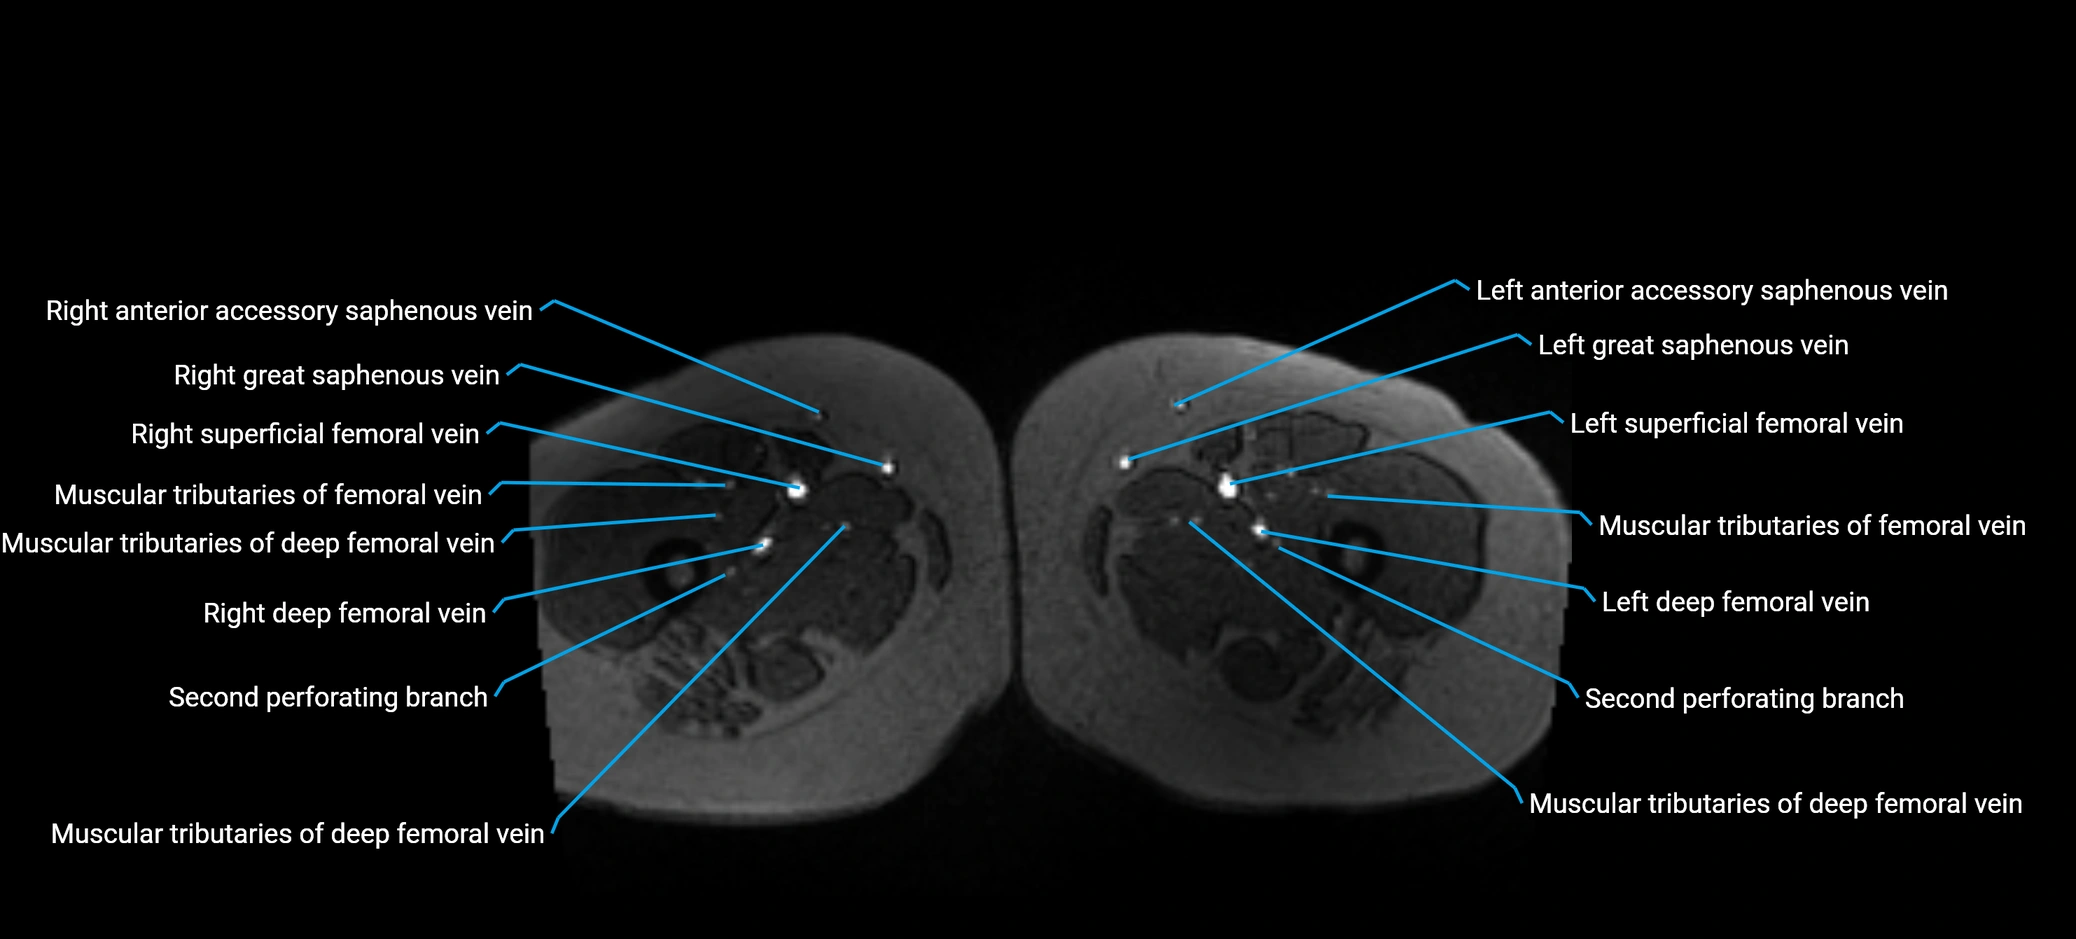

MRI image

image